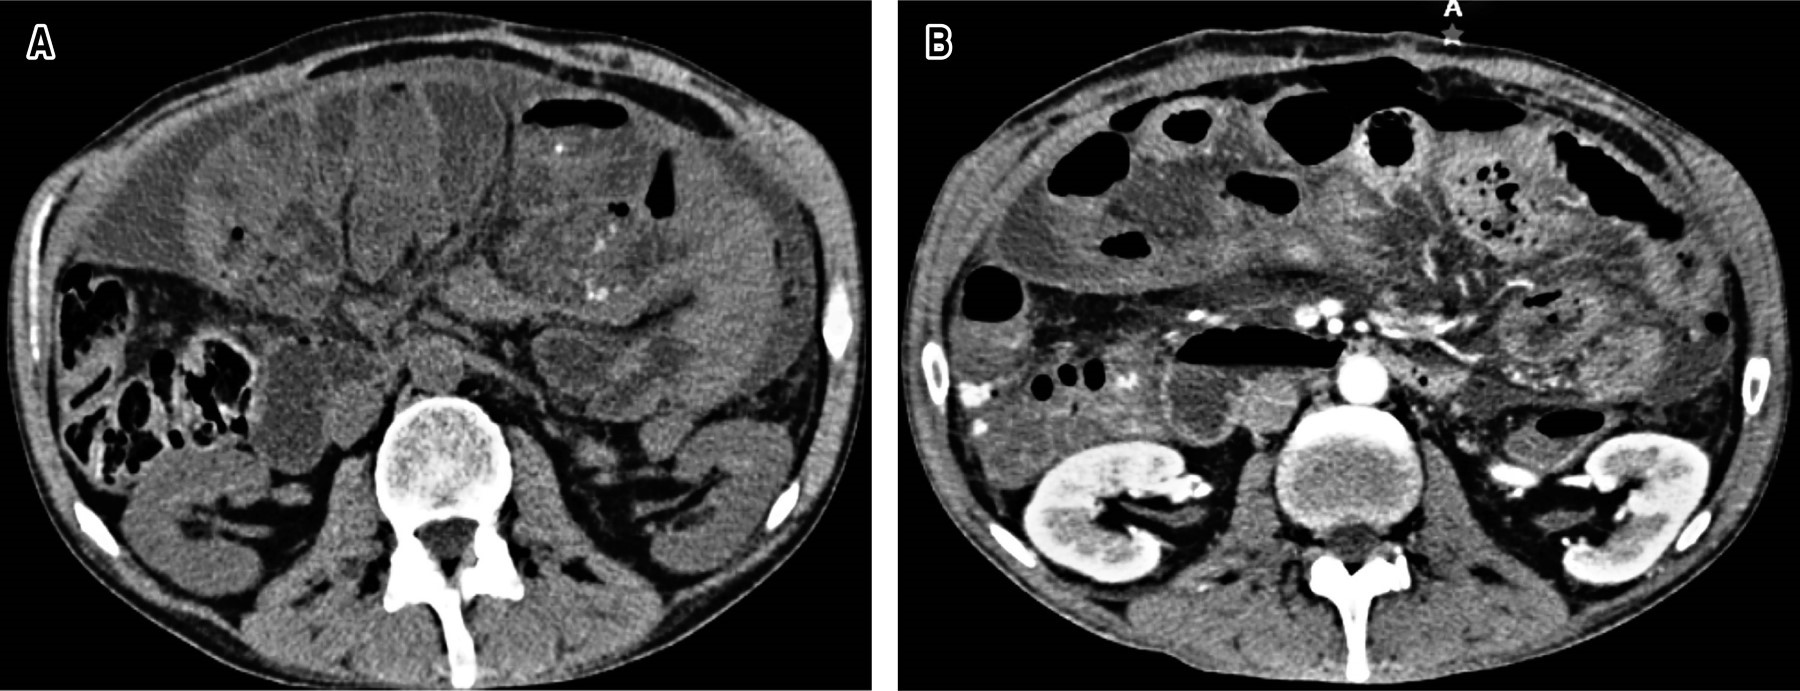

Se ingresa a hospitalización y por sospecha de oclusión secundario a adherencias se decide manejo conservador a base de reposo intestinal, sonda nasogástrica y fluidoterapia con cristaloide, sin embargo, por persistencia de la sintomatología y aumento del dolor abdominal se solicita tomografía abdominopélvica simple reportando distensión de asas de intestino delgado, con punto máximo de dilatación en íleon terminal, así como edema de pared y estriaciones concéntricas por probable intususcepción (Figura 1).

Clínicamente se caracteriza por episodios de oclusión intestinal parcial e intermitente como consecuencia del retorcimiento y compresión del intestino dentro de la membrana fibrosa que lo recubre. En estados crónicos puede presentarse como anorexia y pérdida de peso.1,5 El diagnóstico se sospecha con historia clínica, estudios de gabinete y se confirma durante la cirugía. El estudio de imagen de elección es la tomografía computarizada contrastada, siendo el hallazgo radiológico típico la presencia de un conglomerado de asas de delgado recubiertas por un peritoneo envolvente y engrosado (cocoon sign). Otros hallazgos tomográficos sugestivos son engrosamiento peritoneal, refuerzo peritoneal, calcificaciones y colección líquida loculada.3,6

Como se mencionó en el caso clínico, la primera sospecha respecto a una semiología de este tipo es la oclusión intestinal, motivo por el cual se decidió el manejo conservador, sin embargo, por persistencia de la sintomatología y aumento del dolor abdominal se solicitó lo indicado por la literatura, una tomografía abdominopélvica simple, la cual nos orientó al diagnóstico debido al hallazgo de imagen radiológica característica "signo de cocoon", dando pie al tratamiento quirúrgico en el que se realizó resección completa de cápsula peritoneal, posterior a esto, el diagnóstico histopatológico confirma lo ya descrito por varios autores respecto a la histología y composición de la cápsula.

La peritonitis esclerosante encapsulante o capullo abdominal es una causa infrecuente de oclusión intestinal que se caracteriza por la formación de una membrana fibrocolagenosa difusa del peritoneo. El estudio de imagen de elección es la tomografía computarizada contrastada, siendo el hallazgo radiológico típico la presencia de un conglomerado de asas de delgado recubiertas por un peritoneo envolvente y engrosado (cocoon sign).